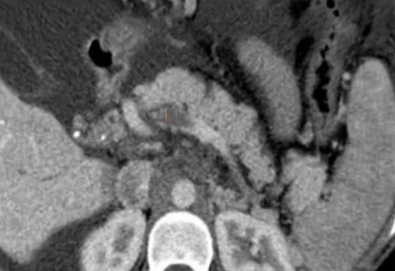

该程序包含以下步骤: 经脾脏入路:在超声引导下,刺穿脾静脉内的一个实质内分支。 在通过脾静脉造影确认了静脉通路后,导管和导丝被推进,以穿过脾静脉并抵达血栓化的门静脉。在门静脉/右门静脉分支处放置圈套器,为TIPS穿刺精准定位。TIPS穿刺圈套器,并穿过圈套器完成TIPS

步骤: 鉴于慢性血栓形成的复杂性: 一种经脾脏途径的门静脉再通术(PVR)。 随后是经颈静脉肝内门体分流术 。

结果:术后影像学检查显示门静脉和脾静脉的血流情况有所改善,且残留血栓极少。

通过经颈静脉肝内门体分流术(TIPS)治疗慢性门静脉血栓时所涉及的技术复杂性和决策难题,尤其是在标准方法因血栓程度过重而无法实施的情况下更是如此。 采用脾经脏穿刺术治疗门静脉高压症的方法证明能够有效克服这些难题,从而成功实施了经颈静脉肝内门体分流术(TIPS)。 PVR-TIPS 作为一线治疗方案:PVR-TIPS 为慢性门静脉血栓的治疗提供了一种技术上可行的解决方案,克服了标准 TIPS 安装所面临的难题。 持久效果:该干预措施不仅恢复了门静脉的血流,而且在后续随访中还显示出持续的通畅性以及血栓的完全消散。